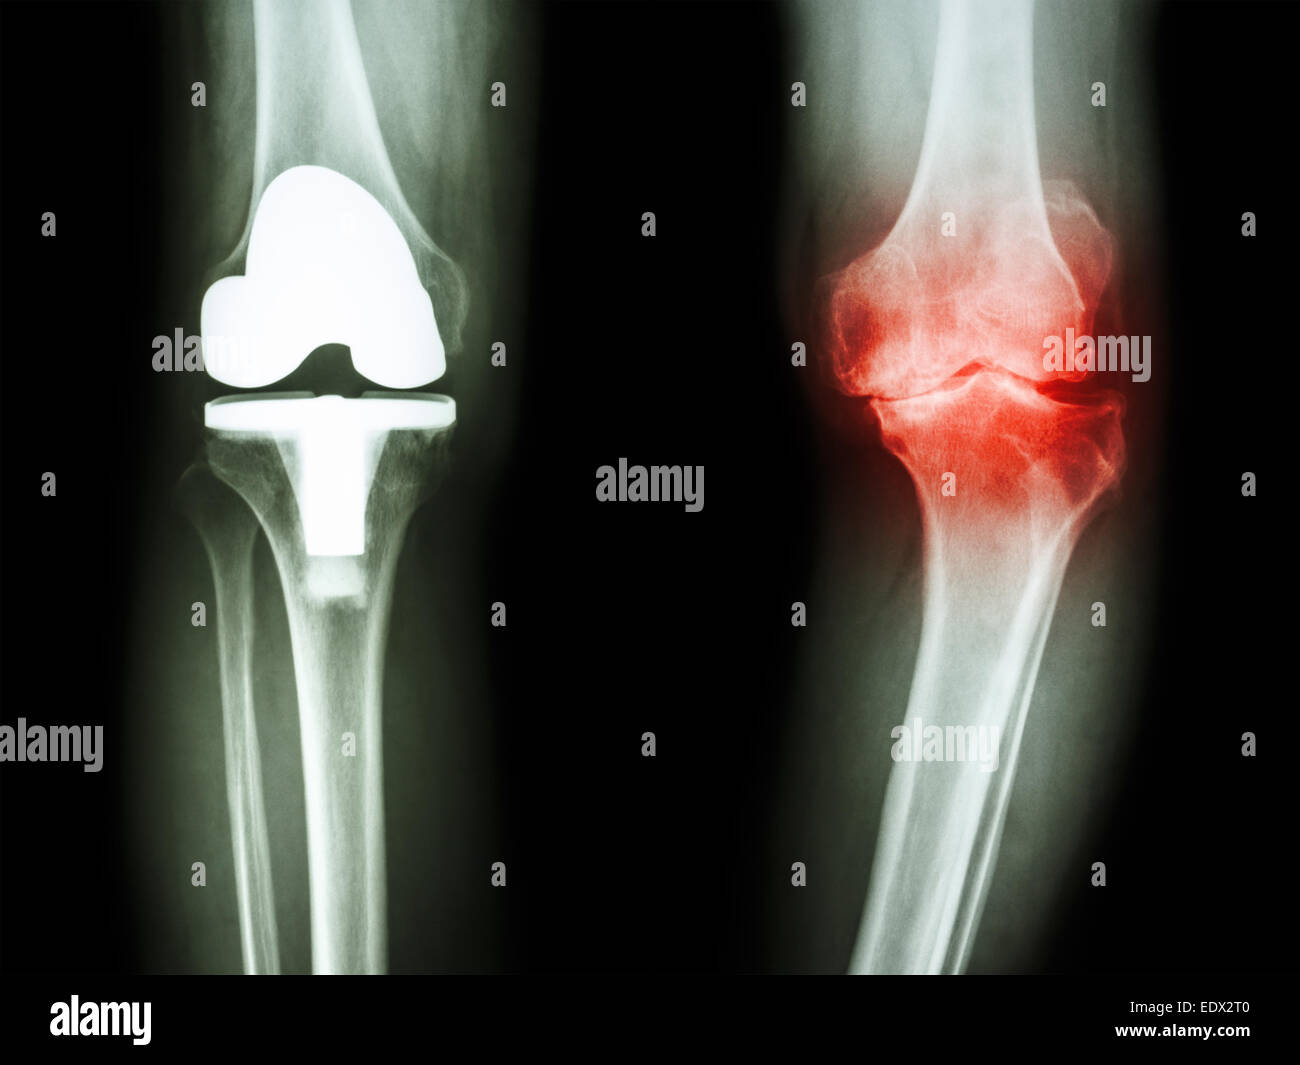

Film x-ray de l'arthrose du genou genou articulation artificielle et patient Banque D'Imageshttps://www.alamyimages.fr/image-license-details/?v=1https://www.alamyimages.fr/photo-image-film-x-ray-de-l-arthrose-du-genou-genou-articulation-artificielle-et-patient-77404991.html

Film x-ray de l'arthrose du genou genou articulation artificielle et patient Banque D'Imageshttps://www.alamyimages.fr/image-license-details/?v=1https://www.alamyimages.fr/photo-image-film-x-ray-de-l-arthrose-du-genou-genou-articulation-artificielle-et-patient-77404991.htmlRFEDX2RY–Film x-ray de l'arthrose du genou genou articulation artificielle et patient

Film x-ray de l'arthrose du genou genou articulation artificielle et patient Banque D'Imageshttps://www.alamyimages.fr/image-license-details/?v=1https://www.alamyimages.fr/photo-image-film-x-ray-de-l-arthrose-du-genou-genou-articulation-artificielle-et-patient-77404992.html

Film x-ray de l'arthrose du genou genou articulation artificielle et patient Banque D'Imageshttps://www.alamyimages.fr/image-license-details/?v=1https://www.alamyimages.fr/photo-image-film-x-ray-de-l-arthrose-du-genou-genou-articulation-artificielle-et-patient-77404992.htmlRFEDX2T0–Film x-ray de l'arthrose du genou genou articulation artificielle et patient